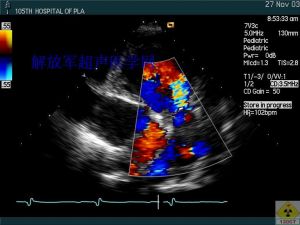

心臟雜音心臟雜音(cordiacmurmur)是指心音及附加心音以外出現的一種非心音性的具有不同頻率、不同強度、持續時間較長的噪雜聲音。它可與心音分開或相連續,亦可完全覆蓋心音。心臟雜音可見於健康人,更多發生於心血管疾病患者。某些雜音是診斷心臟病的主要依據,如在心尖區出現舒張中期伴收縮期前遞增性隆隆樣雜音,可診斷為二尖瓣狹窄。胸骨左緣第2肋間連續性機器樣響亮的雜音,且伴有連續震顫,常提示動脈導管未閉的存在屈而心臟雜育在心臟病診斷中占有極其重要的地位。

患者應取坐位或仰臥位,必要時可囑患者變換體位。如二尖瓣雜音常在左側臥位時聽得清楚;主動脈瓣關閉不全的雜音於坐位或站立位時更為清晰。聽診時還應注意雜音在心動周期中的時間(收縮期或舒張期)、最響的部位、音調高低、響度、音質(吹風樣、隆隆樣、機器聲樣、樂音樣)、是否傳導、傳導的方向、與運動、呼吸。體位和藥物影響的關係等來判斷其臨床意義。

心臟雜音如果懷疑雜音是病理性的,則需確定有無器質性心臟病,何種器質性心臟病,心臟的功能情況等。因此,需進一步做胸片、心電圖、心音圖、超聲心動圖等檢查,以便醫生綜合資料對病情作出確切的估計。凡是感染發熱、貧血、甲狀腺功能亢進或高血壓等全身性疾病導致的心臟雜音,應該治療這些全身性疾病,待疾病好轉後雜音即可減弱,以至消失。